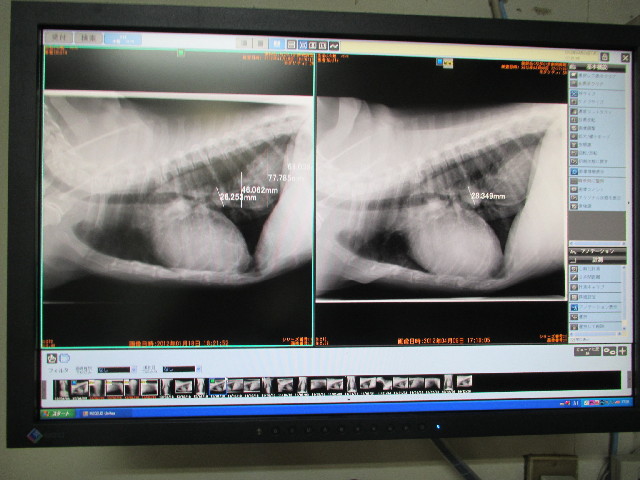

暖かくなったのと、トシで動くのにも力が入るせいだと思うのですが最近ハアハアすることがあるのでレントゲンをとってもらいました。

(2mm以下だと写らないが)肺への転移はないとのこと(^-^)v

左は1月18日で、右が今日(4月9日)

右の画像のQちゃんの手前の白いもの(28.349mmと書いてある部分)は、なんとか(忘れちゃいました(ToT)ゞ)で、新しい腫瘍等ではないって。